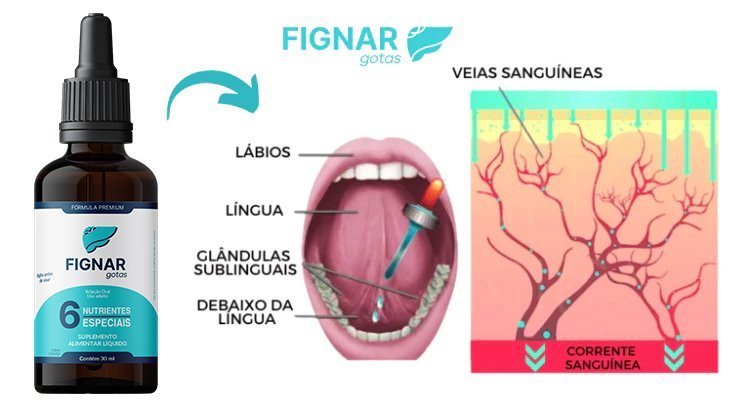

O Fignar Gotas é um dos primeiros produtos do mundo projetados para atingir um fígado sobrecarregado, promovendo a remoção de toxinas, perda de peso saudável e melhorando a função hepática.

O Fignar Gotas é um mix de componentes naturais que trazem diversos benefícios para a saúde!

A exclusiva tecnologia AMERICANA de aplicação sublingual proporciona uma absorção rápida e eficaz por meio da glândula que temos sob a língua , nela vasos que acessam diretamente a corrente sanguínea absorvem rapidamente seu conteúdo e promovem resultados surpreendentes em pouquíssimo tempo, essa é a forma mais eficaz, garantindo até 98% de absorção dos ativos da composição.